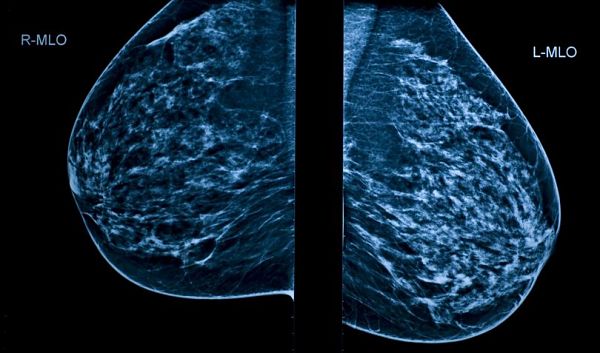

En Reino Unido, una de cada ocho mujeres han recibido el diagnóstico de cáncer de mama en algún momento de su vida. Se trata de uno de los tipos de cáncer más comunes, así que cualquier labor de investigación es poca. El programa podrá aplicarse en todas aquellas mujeres que tengan antecedentes familiares de cáncer de mama (y por lo tanto, united nations riesgo potencial de sufrir la enfermedad) y es capaz de interpretar de una manera muy fiable las mamografíequally que se realizan habitualmente como prevención y para el diagnóstico. Esta información es procesada de tal manera que el programa es capaz de diagnosticar hasta xxx veces más rápido que un humano y lo que es más importante, con una pasmosa precisión de un 99 por ciento.

Lo que hace el software, además, es revisar de manera inteligente todos los registros que existen en un corto período de tiempo, de modo que cualquier evolución o cambio en la morfología mamaria puede ser detectado con mucha más precisión y acierto. Para Stephen T Wong, director del Departamento de Medicina de Sistemas y Bioingeniería, los avances que podrá ofrecer este software son muy importantes, porque ante cualquier sospecha, podrán reducirse el número de biopsias que al final terminan siendo innecesarias.

De momento, el software ya ha evaluado un full de 500 pacientes. Con este se recogen las características de cada diagnóstico y los resultados de la mamografía correlacionados con cada subtipo de cáncer de mama. Cuando un médico observa una masa o una evolución sospechosa en el pecho a través de una mamografía, lo que suele hacerse es una biopsia. Las biopsias son procedimientos muy efectivos, pero invasivos, que recogen tejido o fluidos de una área sospechosamente afectada por células cancerosas. De este modo, las células se pueden analizar en laboratorio y los equipos médicos pueden dar diagnósticos certeros. Sin embargo, el xx % de estas biopsias son procedimientos innecesarios, porque los resultados son negativos.